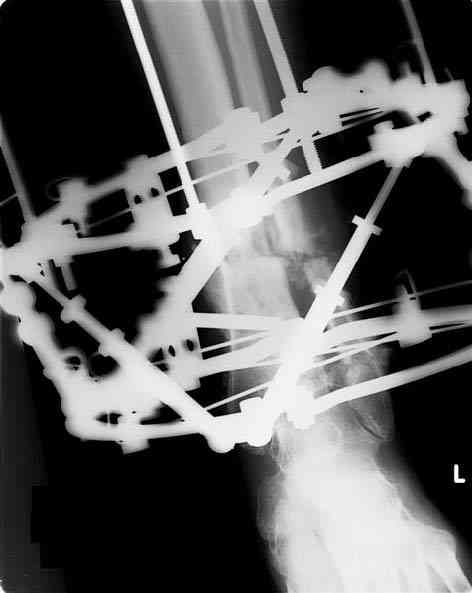

Sorry, I wiil tray now pictures of my case.